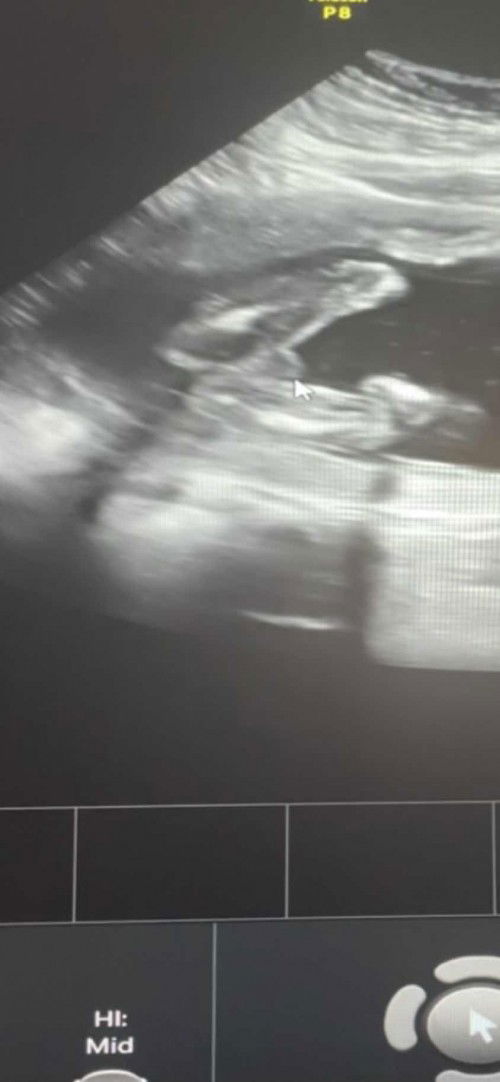

scan weeks berapa ni awak. kalau gugurl akan nampak 3line dan symbol burger. gugurl paling susah detect bila scan. boboy kadang sekali scan dh nmpk pistol dia

mcm boy nmpknya.. doktor ada bgtau ke tu.. pape pon semoga mummy n kandungn sihat ya🥰

Doktor cakap boy. Hehe thankyou sis . Semoga sis pun sihat 🥰🥰

Macam boy 👶🏻

boy ni😁😁🥰

Mcam boy. Heheh

mcm boboy ni 🥰